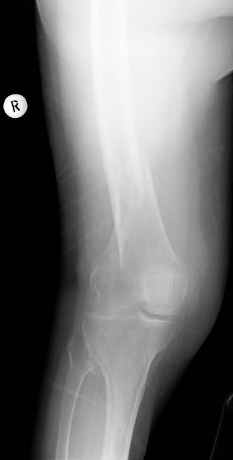

Видно спиральный перелом дистального метадиафиза бедра. У нас бы сделали антеградный закрытый интрамедуллярный остеосинтез.